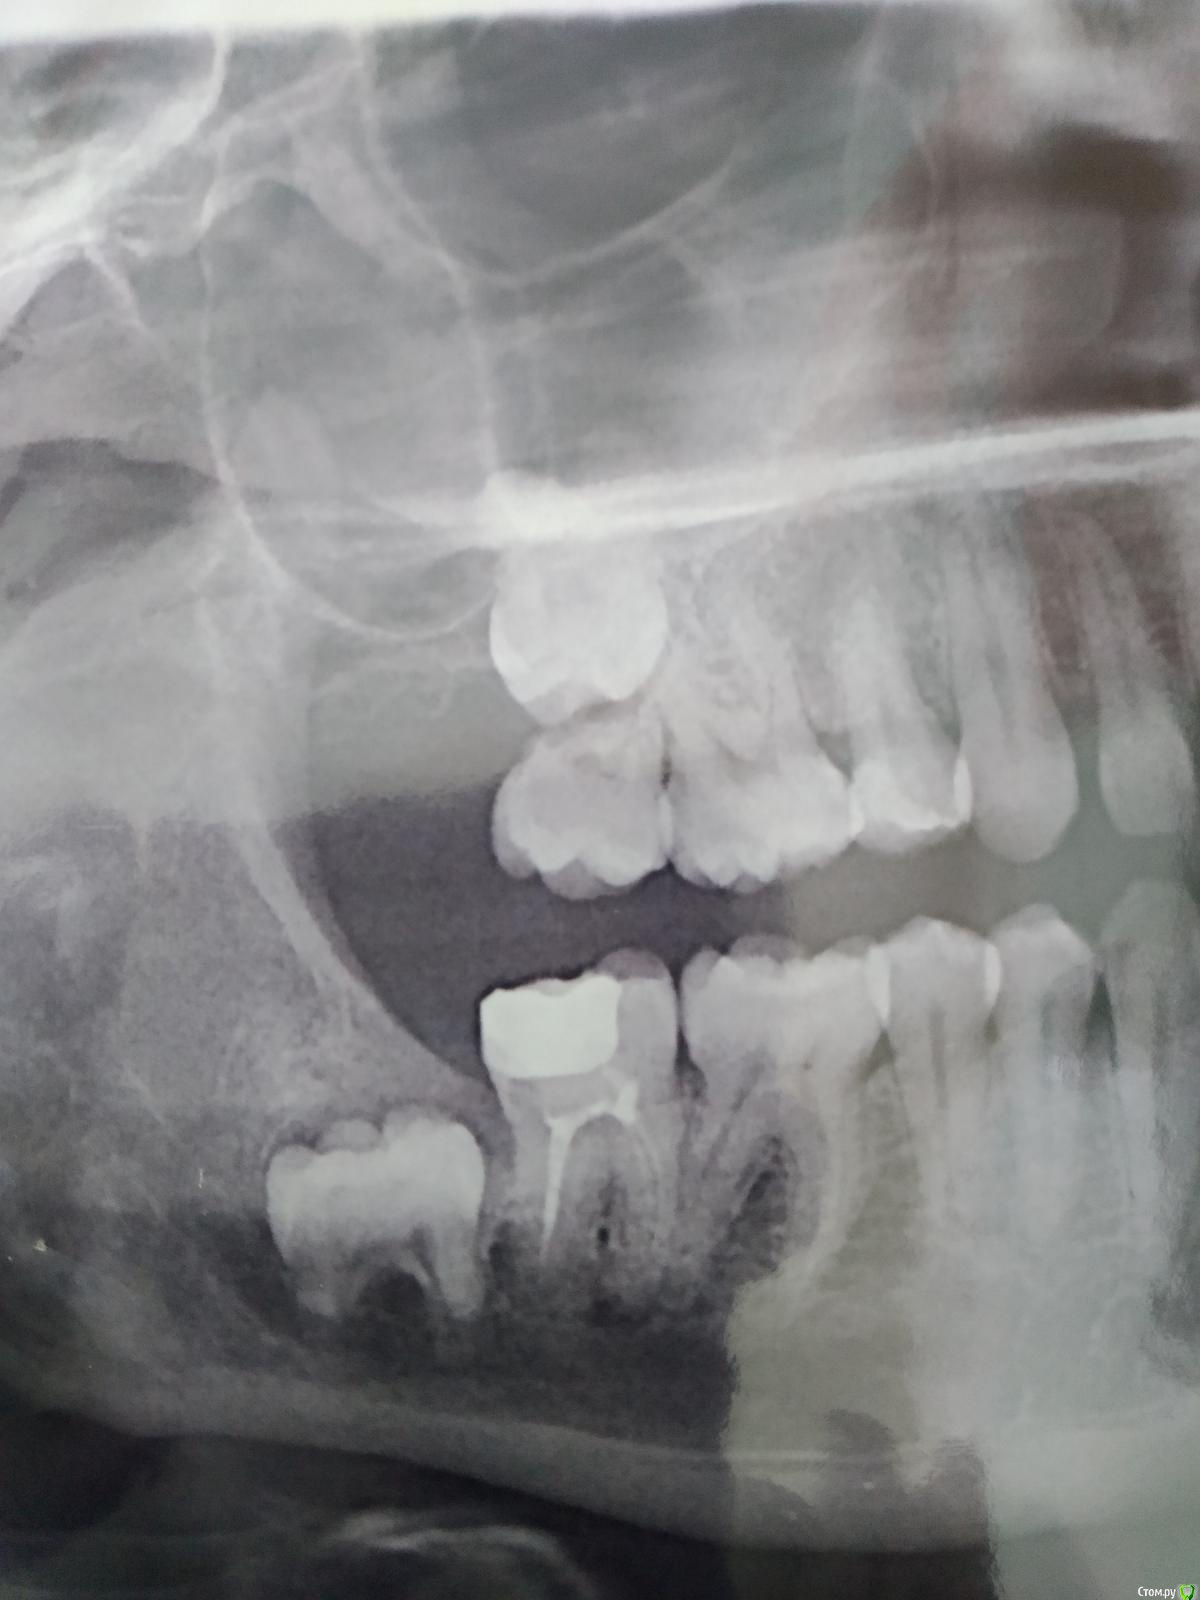

shishok Опубликовано 1 июля, 2020 Поделиться Опубликовано 1 июля, 2020 Пациента беспокоят периодические боли в 17 при приеме жесткой пищи. Визуально всё в норме, перкуссия на момент осмотра б/б.На ОПТГ вот такая картина.Надеюсь,что восьмерка встанет на место 17. Ссылка на комментарий

vse32 Опубликовано 1 июля, 2020 Поделиться Опубликовано 1 июля, 2020 А я смотрю на верху еще и премоляра не хватает. Не повезло прямо. Ссылка на комментарий

shishok Опубликовано 2 июля, 2020 Автор Поделиться Опубликовано 2 июля, 2020 А я смотрю на верху еще и премоляра не хватает. Не повезло прямо.Верхние пятёрки были вторым рядом небно.Удалены лет 10 назад. Ссылка на комментарий

Kolchanov Опубликовано 2 июля, 2020 Поделиться Опубликовано 2 июля, 2020 31 год.Что-то я сомневаюсь тогда, что восьмерка там прорезается. Если только какой суперортодонт вытащит. Ссылка на комментарий

Brigita Опубликовано 3 июля, 2020 Поделиться Опубликовано 3 июля, 2020 встанет. Ну и судя по резорбции корней 7ки он реально двигается, все не случайно.Если не встанет за полгода - ортодонт вытянет. Там скорее всего ортодонтия нужна и без 8и Ссылка на комментарий

annda Опубликовано 4 июля, 2020 Поделиться Опубликовано 4 июля, 2020 Ну прям молочная 7ка) Ссылка на комментарий